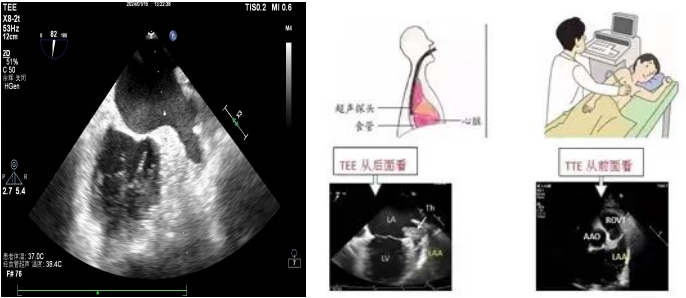

左心耳位于左心房的偏后上部分,大部分情况下被左心房主体部分遮挡,常规的经胸超声心动图(TTE)很难清晰显示。TEE是超声探头置入食道内,从心脏的后方进行检查,缩短了超声探头与心脏及距离,避免了肺气干扰、肋骨遮挡等弊端,可直观的从左心房看到左心耳,排查左心耳内有无血栓。目前我院开展了常规经食道超声心动图和无痛经食道超声心动图检查。